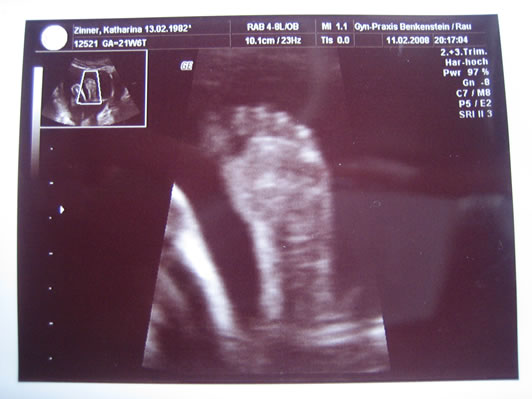

Mama spürt mich mittlerweile auch jeden Tag mehrmals, mach mich ja auch oft genug mit Rollen, Verrenkungen und Schluckaufs bemerkbar. Papa hör ich jetzt oft an Mamis Bauch mit mir reden und knutschen, ich mach mich dann auch wie wild bemerkbar, leider spürt er das noch nicht so wie die Mama. Da ich grad müde werd, zum Schluß für heute für alle Neugierigen noch ein Bild eines meiner Füße.